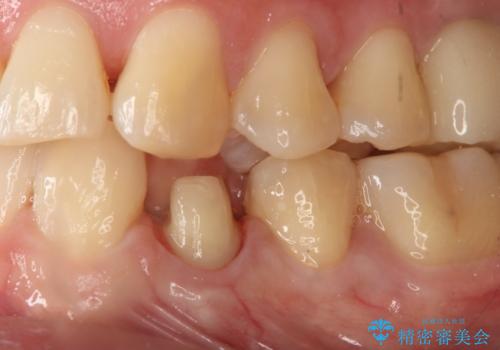

- 左下4番のう蝕を指摘され治療を希望された患者様です。

切削量などを考慮しクラウンでの治療を提案したところ、セラミックを希望されたのでフルジルコニアクラウンでの治療を選択しました。

う蝕が深かったので痛みが出る可能性をお伝えしましたが特に症状は現れなかったので、予定通りセラミッククラウンでの治療を行いました。